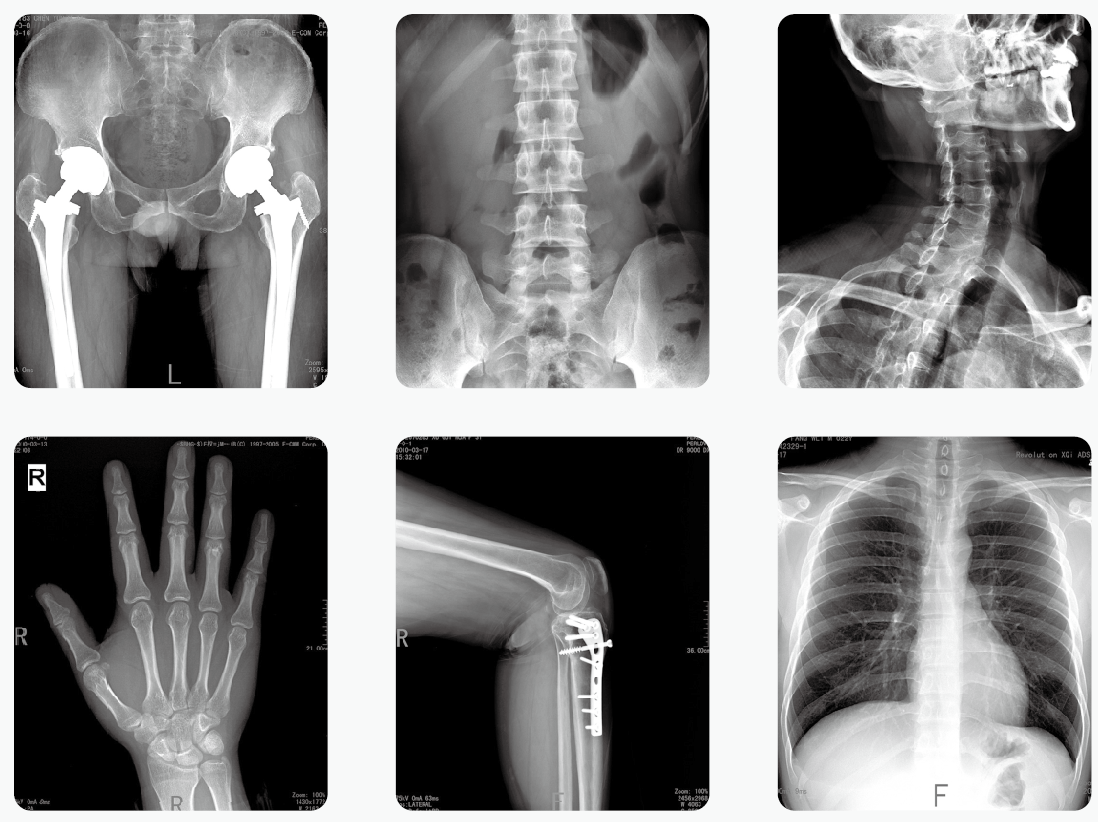

短期大劑量或長期小劑量接受放射檢查輻射,累積效應(yīng)可能導(dǎo)致細(xì)胞突變,與惡性腫瘤發(fā)病率正相關(guān),這已成共識。所以,不以劑量為前提談輻射危害都是在耍流氓!那么,多少劑量的輻射是安全的,是在可接受的范圍內(nèi)?

了解輻射的危害先要大概知道多大的輻射是相對安全的。人在地球上每時每刻都在接受輻射,輻射按照來源可以分為天然輻射和人工輻射。天然輻射就是來自大自然的輻射,包括太陽、空氣、地層等等散發(fā)的輻射。人工輻射則是人為制造的輻射,比如醫(yī)療器械檢查的輻射,核電站的輻射等。

世界衛(wèi)生組織的標(biāo)準(zhǔn)是:人體每年接受的輻射量不要超過5mSv(毫希伏)。

大家在單位例行體檢時一般會拍X光胸片,它的輻射量大約是0.1mSv;而做一次低劑量CT胸片是1mSv。

其實,大多數(shù)市民一年中也就是在體檢的時候才會接觸放射性檢查,不必過于擔(dān)憂。

那么,如何減少放射檢查的影響?

明白放射檢查沒那么可怕之后,再來談?wù)勅绾螠p少這類檢查對人體的影響。醫(yī)生在為患者進(jìn)行放射性檢查時,會遵循以下原則:

1、當(dāng)患者的表面癥狀不足以確診疾病,或者需進(jìn)一步確定疾病的程度時,醫(yī)生確實需要借助X光機(jī)和CT等來明確診斷,才會開出檢查單。而且每一項檢查都有嚴(yán)格的適應(yīng)癥,會讓患者做對應(yīng)的檢查。

2、盡量選擇輻射小的檢查項目:能用低劑量技術(shù)的就不用高劑量技術(shù);能用X線解決的就不用CT;每年必要的體檢盡量不做常規(guī)CT,而做低劑量CT篩查。

3、做放射性檢查時規(guī)范操作,對非檢查部位、重要部位采取嚴(yán)格的防護(hù)措施。如做胸部X線檢查,腹部、甲狀腺等部位會用鉛衣等防護(hù)設(shè)備予以保護(hù)。

除此之外,避免多次重復(fù)檢查;備孕女性、懷孕3個月內(nèi)的女性,以及兒童等特殊群體,應(yīng)少接觸或根本不接觸放射檢查。懷孕3個月之后,如果病情確實需要通過放射性檢查來診斷,在做好必要的防護(hù)之后,建議該檢查的還是得檢查,以免延誤治療。